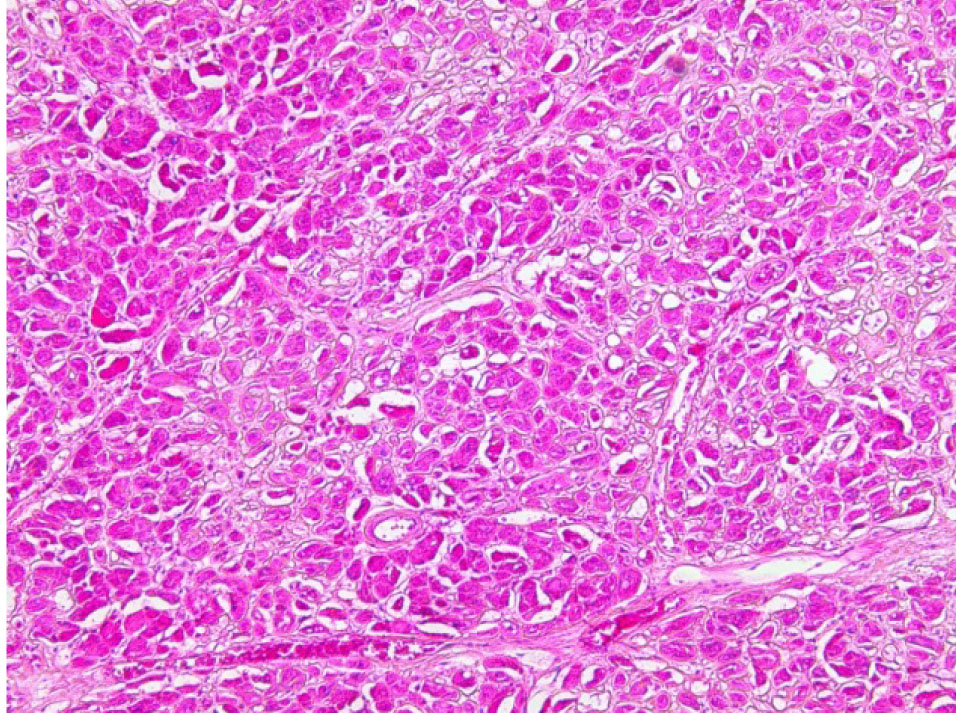

Гистологическое исследование. Сердце – кардиомиоциты гипертрофированы, диффузный кардиосклероз. При окраске на амилоид в строме и стенке сосудов отложение амилоидных масс (рис. 1). Селезенка – красная пульпа полностью замещена однородными массами, дающими положительную окраску на амилоид (рис. 2).

Рис. 2. Амилоид в красной пульпе селезёнки. Окраска конго красный, ×200